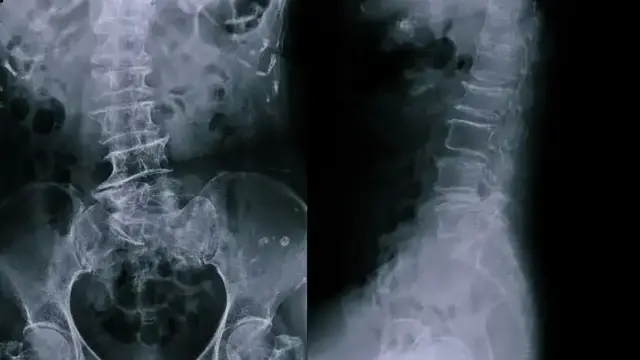

След направена рентгенова снимка лекарите откриват изненадващата причина за проблема – керамична чаша с размери 8 х 6 см, намираща се дълбоко в ректума. По думите на мъжа всичко се е случило „случайно“, но той отказал да даде повече подробности.

Тъй като предметът не е могъл да бъде изваден по естествен път, медицински екип е извършил двучасова операция за безопасното му отстраняване през храносмилателния тракт. Пациентът преди това безуспешно е опитвал сам да реши проблема.